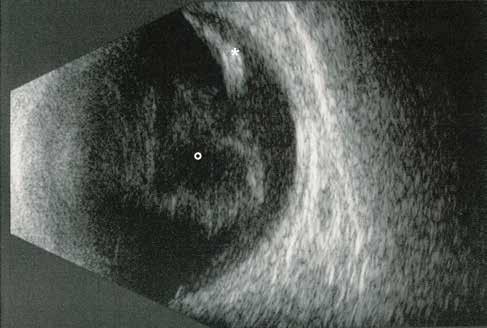

Diabetic retinopathy (DR) is the most common ocular manifestation of diabetes and the leading cause of blindness among the working-age population in industrialized countries. (1) Clinically, DR is classified as non-proliferative (NPDR) and proliferative diabetic retinopathy (PDR), based on the development of anomalous new blood vessels on the retina, optic disc, or iris. Late-stage complications are vitreous hemorrhages, tractional retinal detachment, and neovascular glaucoma. However, the most prevalent cause of vision loss is diabetic macular edema (DME), which may affect all stages of the disease. (2)

Early non-proliferative microvascular damage includes thickening of the basement membrane, disruptions of the tight junctions and loss of pericyte clinically corresponding to microaneurysms and intraretinal hemorrhages (dot, blot, flamed-shaped). Subsequently, hypoxia and capillary occlusion are favored by the predominance of vasoconstrictors agents and maladaptive vascular remodeling. Thus, severe NPDR displays retinal ischemia starting from periphery towards the macula (diabetic macular ischemia, [DMI]), retinal infarction (cotton wool spots), dilated capillaries and shunts between arteries and veins (intraretinal microvascular abnormalities, [IRMA]) and anomalous veins (dilated, tortuous and irregular in caliber). In late stages of PDR, the hypoxic environment creates an imbalance of angiogenic (e.g. VEGF) over anti-angiogenic (e.g. PEDF) mediators, resulting in neovascularization (NV) sprouting on the optic disc (NVD), the retina, the iris and the angle (neovascular glaucoma). Due to their structural weakness, these new vessels are more likely to bleed spontaneously (vitreous and preretinal hemorrhage), and adhere to the vitreous body. Over time, adventitial fibrotic component develops and contracts, forming epiretinal membranes (ERM), vitreomacular traction (VMT), and ultimately tractional retinal detachment. (2,3) Notably, DME may occur during both NPDR and PDR. DME manifests as retinal thickening due to the accumulation of intraretinal fluid and/or extracellular lipid leakage (hard exudates) in the outer plexiform layer. Several mechanisms, including VEGF, have been proposed, all converging on the internal breakdown of the BRB due to increased capillary permeability and vascular leakage (10) Additionally, vitr-